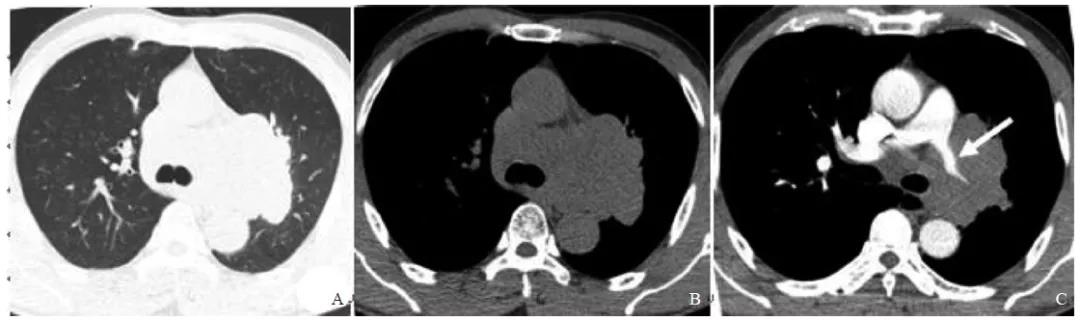

[摘要] 目的:探讨肺原发性小细胞神经内分泌癌(lung primary small cell neuroendocrine carcinoma,LSCNC)的C...